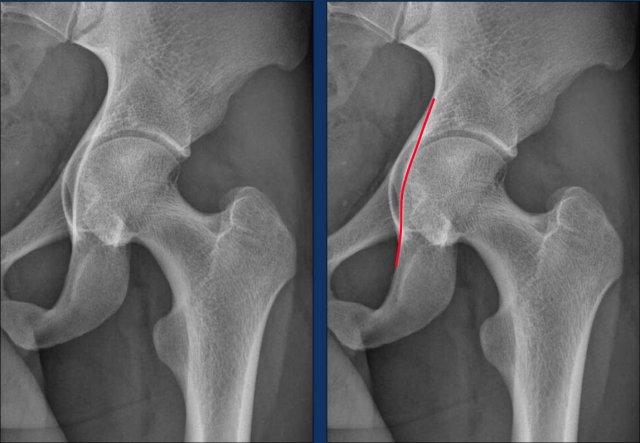

Phẫu thuật nội soi khớp

Nếu các biện pháp này không hiệu quả, có thể cân nhắc can thiệp phẫu thuật. Trước khi phẫu thuật, chụp cộng hưởng từ khớp thường được thực hiện để đánh giá tình trạng của sụn viền và loại trừ các bệnh lý có thể xảy ra khác, chẳng hạn như tổn thương sụn khớp nặng hoặc phù tủy xương vô căn. Các rách sụn viền nhỏ thường không được điều trị, trong khi các rách lớn không ổn định có thể được cắt bỏ hoặc sửa chữa. Trong quá trình phẫu thuật, phần xương thừa của hình thái cam ở phía xương đùi của viền ổ cối có thể được loại bỏ. Quá trình phục hồi chức năng sau phẫu thuật mất nhiều thời gian và thường phải mất ít nhất 9 tháng để trở lại thi đấu thể thao ở cấp độ cao.

Hình ảnh

Ở một bệnh nhân có hình thái Cam, có thể thấy hiệu quả của việc tạo hình lại vùng tiếp nối đầu-cổ xương đùi (mũi tên).

Examples of FAI

Combination of Cam and Pincer morphology

Những hình ảnh này là của một phụ nữ 28 tuổi tham gia tập CrossFit ở cấp độ chuyên nghiệp. Cô ấy đã có các triệu chứng ở vùng hông trái, cụ thể là ở phía trước, trong suốt một năm qua. Các triệu chứng trở nên nặng hơn khi thực hiện động tác squat và gấp hông.

Khi thăm khám, ghi nhận giảm biên độ gấp háng (đau ở 120°) và hạn chế xoay (giới hạn ở 20° và đau).

Đầu tiên hãy nghiên cứu hình ảnh X-quang.

Sau đó tiếp tục với các hình ảnh chi tiết…

Mặc dù các phát hiện còn tinh tế, nhưng có bằng chứng về hình thái Pincer, được chỉ ra bởi dấu hiệu giao thoa và dấu hiệu gai ngồi.

Sự xoay ngược của ổ cối dẫn đến gai ngồi nổi bật hơn và khiến phần trên của thành trước ổ cối chồng lên thành sau trên hình ảnh.

Ngoài ra, có dấu hiệu nhẹ của hình thái Cam.

Continue with the MR-arthrogram…

Sau đó, chụp cộng hưởng từ khớp được thực hiện, cho thấy rách sụn viền ở vùng trước trên.

Ban đầu, bệnh nhân được điều trị bảo tồn bằng vật lý trị liệu, nhưng kết quả không đạt yêu cầu.

Sau đó, một thủ thuật nội soi khớp đã được thực hiện, bao gồm việc tạo hình lại chỗ nối chỏm-cổ xương đùi (mũi tên), mang lại sự cải thiện đáng kể.